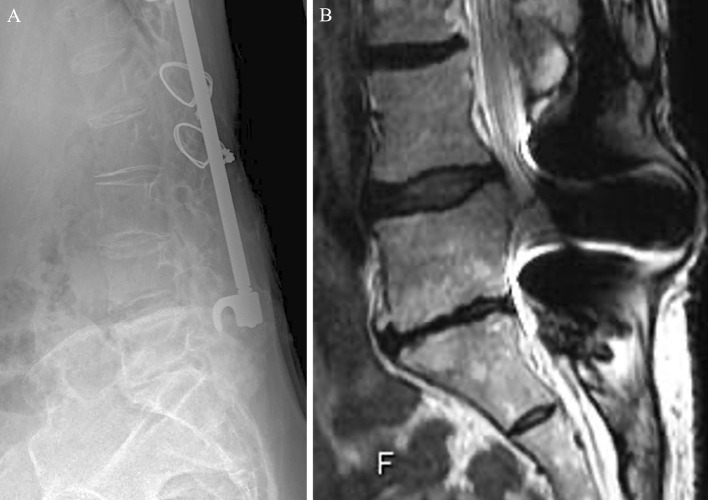

简介:本研究旨在确定中老年青少年特发性脊柱侧凸(AIS)患者术后椎间盘退变(DD)的相关因素。方法:在1968年至1988年期间接受脊柱融合手术的252名AIS患者被纳入这项基于调查的研究。患者的平均随访期为40.9年,通过腰椎磁共振成像(MRI)、放射学评估和患者报告的结果测量(PROMs)对患者进行评估。采用Pfirrmann分级系统对DD进行评价。我们分析了手术水平、矢状面对准和前列腺癌等各种因素与DD的关系。结果:在21名接受了先前(2014年至2016年)和最新(2022年)调查的参与者中,DD的患病率从上一次调查的66.7%上升到最新调查的76.9%。Pfirrmann disc总分从3.2显著提高到3.5。矢状面排列参数,如矢状垂直轴(SVA)、骨盆发生率减去腰椎前凸(PI-LL)和骨盆倾斜(PT),随着时间的推移而恶化。脊柱侧凸研究学会-22疼痛问卷、Roland-Morris失能问卷、Oswestry失能指数得分均较前一次明显下降。L4或更低和L3或更高的下固定椎体(LIV)患者的比较显示,L4或更低组的椎间盘评分明显更高,DD患病率为100%。与DD相关的因素包括L4或更低的LIV,较小的LL,较大的胸腰椎后凸,SVA, PI-LL和pt增加。结论:本研究表明,维持L3或更高的LIV,实现良好的矢状位对齐,维持LL可能有助于预防AIS患者的长期DD。

Results: Among the 21 participants who underwent both previous (conducted from 2014 to 2016) and latest surveys (conducted in 2022), the prevalence of DD increased from 66.7% in the previous survey to 76.9% in the latest survey. The overall Pfirrmann disc score significantly increased from 3.2 to 3.5. Sagittal alignment parameters, such as sagittal vertical axis (SVA), pelvic incidence minus lumbar lordosis (PI-LL), and pelvic tilt (PT), worsened over time. Scores in the Scoliosis Research Society-22 Questionnaire pain, Roland-Morris Disability Questionnaire, and Oswestry Disability Index were significantly worse in the latest survey than in the previous one. Comparison between patients with the lower instrumented vertebra (LIV) at L4 or lower and L3 or higher revealed significantly higher disc scores and 100% prevalence of DD in the L4 or lower group. Factors associated with DD included LIV at L4 or lower, smaller LL, larger thoracolumbar kyphosis, and increased SVA, PI-LL, and PT.